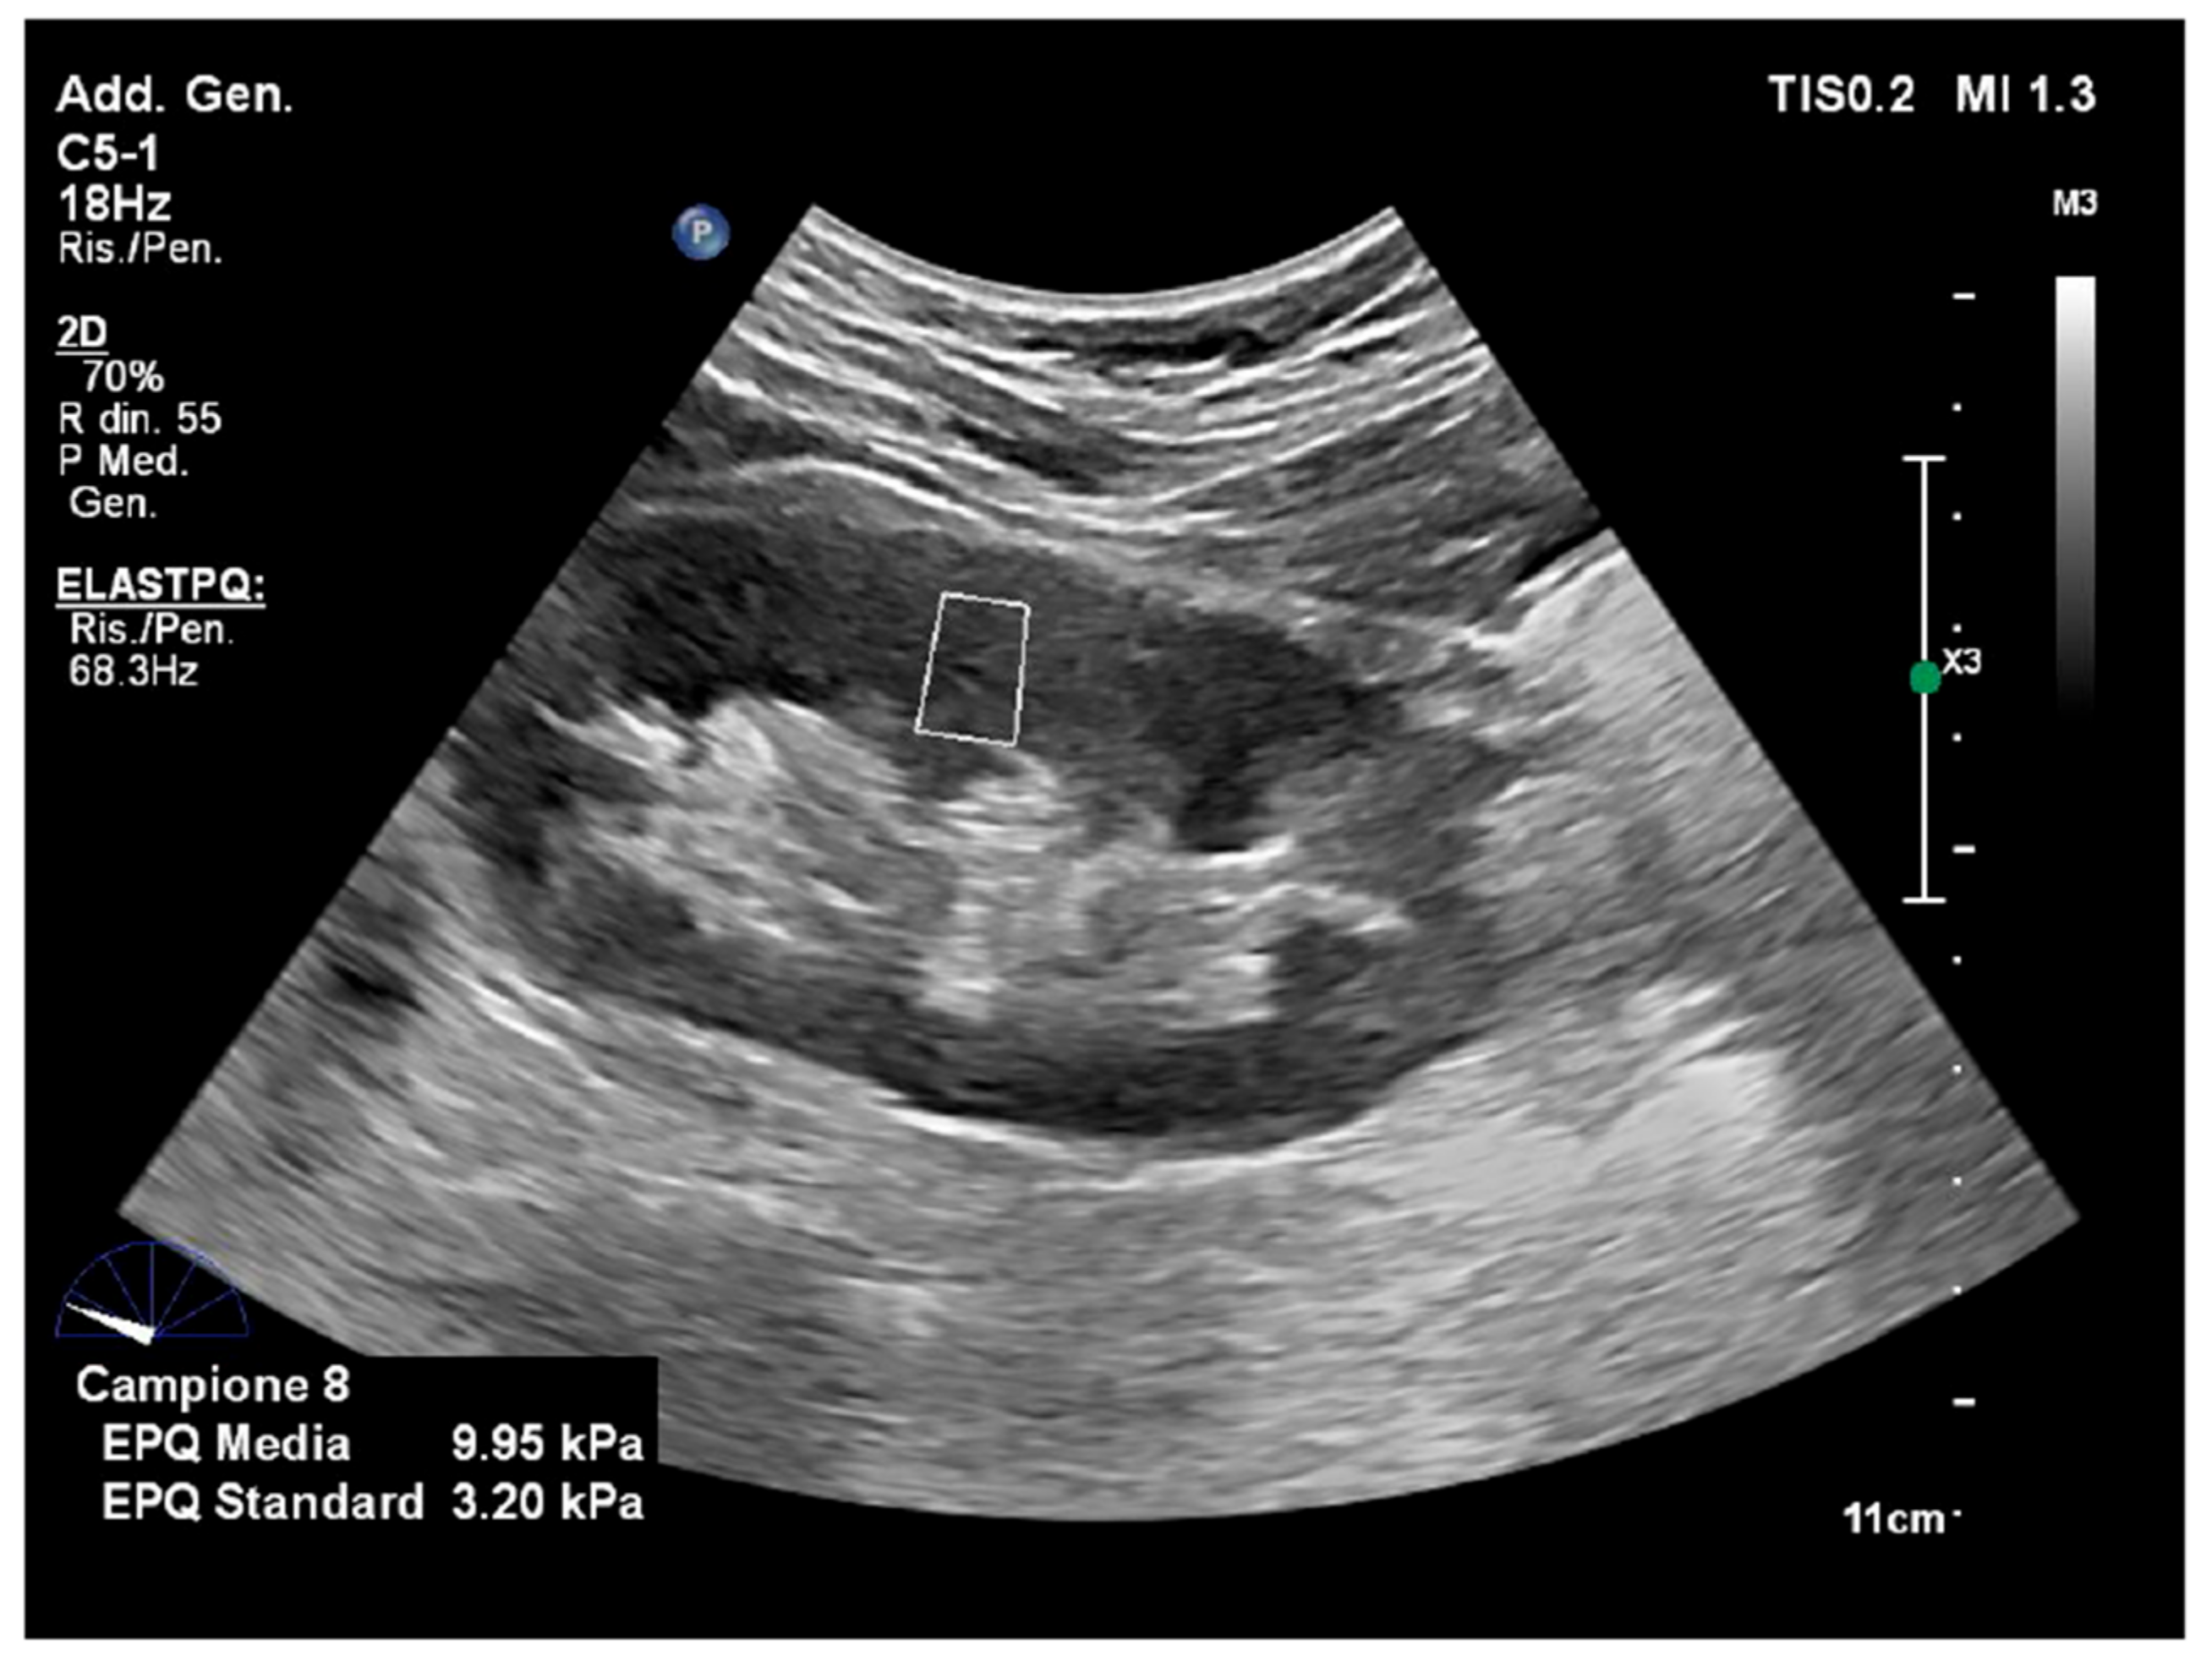

4.1. Liver

- Yazaki, T.; Tobita, H.; Sato, S.; Miyake, T.; Kataoka, M.; Ishihara, S. Combinational elastography for assessment of liver fibrosis in patients with liver injury. J. Int. Med. Res. 2022, 50, 3000605221100126. [Google Scholar] [CrossRef] [PubMed]